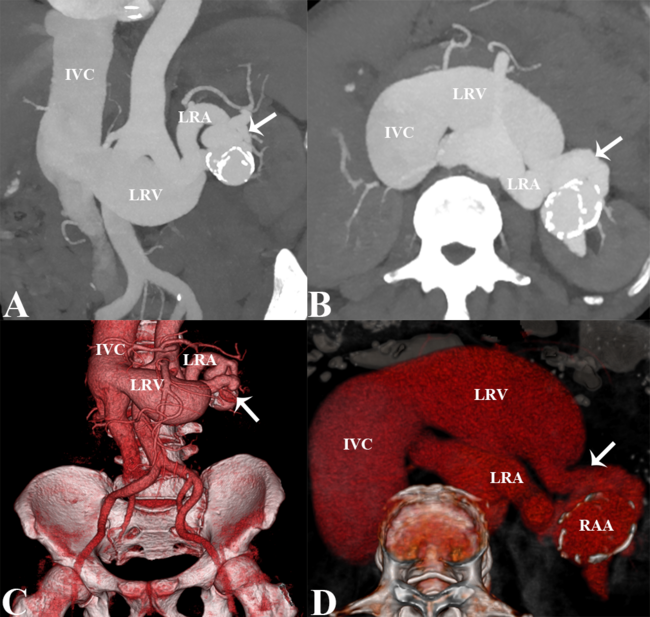

A 46-year-old man presented with bilateral lower extremity edema for more than 3 months. He had a history of bruising to the left abdominal area as a result of a motorcycle accident several years ago. Cardiac auscultation revealed a hyperactive P2 heart sound and a grade 2/6 systolic murmur between the second and third intercostals on the left side of the sternum. Laboratory tests revealed a hemoglobin level of 108 g/L (reference range, 130-170 g/L) and a pro-brain natriuretic peptide (BNP) level of 2991 pg/mL (reference range, <125 pg/mL). The electrocardiogram was unremarkable. Transthoracic echocardiography showed whole heart enlargement, severe tricuspid valve insufficiency, and moderate pulmonary hypertension. Computed tomography angiography (CTA) images suggested a giant left arteriovenous fistula (AVF) with renal artery aneurysm (RAA) (Figure A-D), and angiography showed a giant left AVF with RAA (40.5 x 30.7 mm) and a dilated and elongated renal artery (Video). After a comprehensive preoperative assessment, the patient was recommended for a surgical approach, but he refused the procedure.